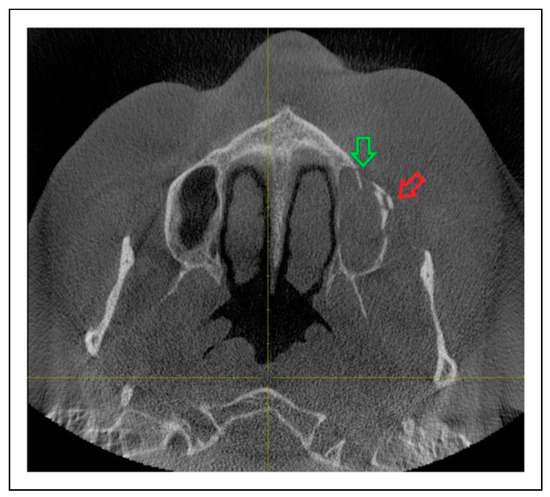

Patterns of ZMO Fractures Regarding the Anatomic Sutures of the Zygoma

- Unisutural fracture (isolated fracture of a single anatomic suture of the zygoma):

- Zygomaticomaxillary suture (ZM)

- Infraorbital rim (IOR)

- Zygomaticofrontal suture (ZF)

- Zygomaticosphenoidal suture (ZS)—the anterolateral orbital floor

- Zygomaticotemporal suture (ZT)

- Bisutural fracture with the following fracture line combinations: